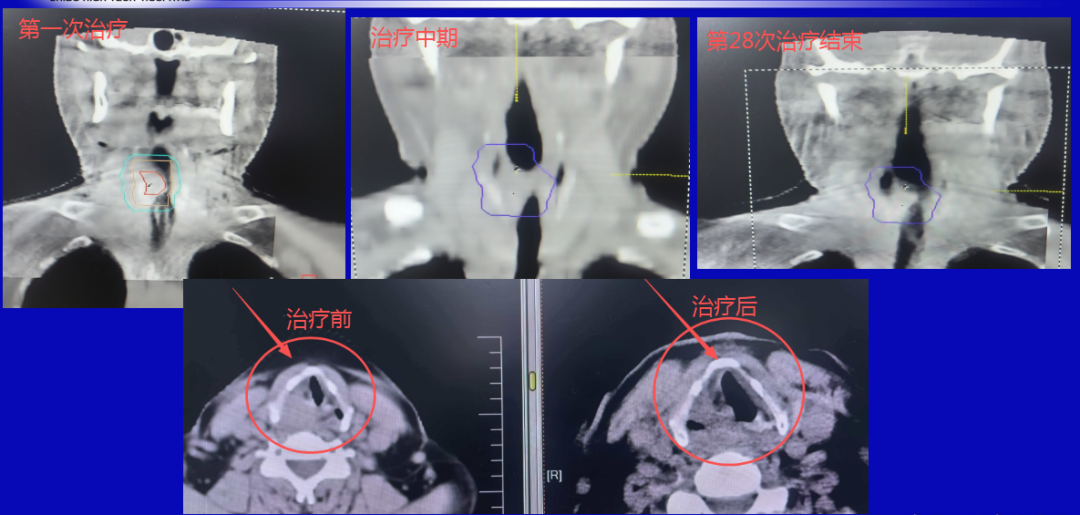

2. 喉部病灶:直线加快器——控瘤同期保功能

喉部病灶的诊治,则接纳了直线加快器。通过多叶准直器收尾三维适形调强放疗,射线可精确“塑形”,均匀隐蔽喉部肿瘤,同期灵验躲避食管、气管等弥留器官。

在高效边界局部病灶的同期,最猛进度保留患者的吞咽、发声功能,保险后续生计质料。

喉部复查